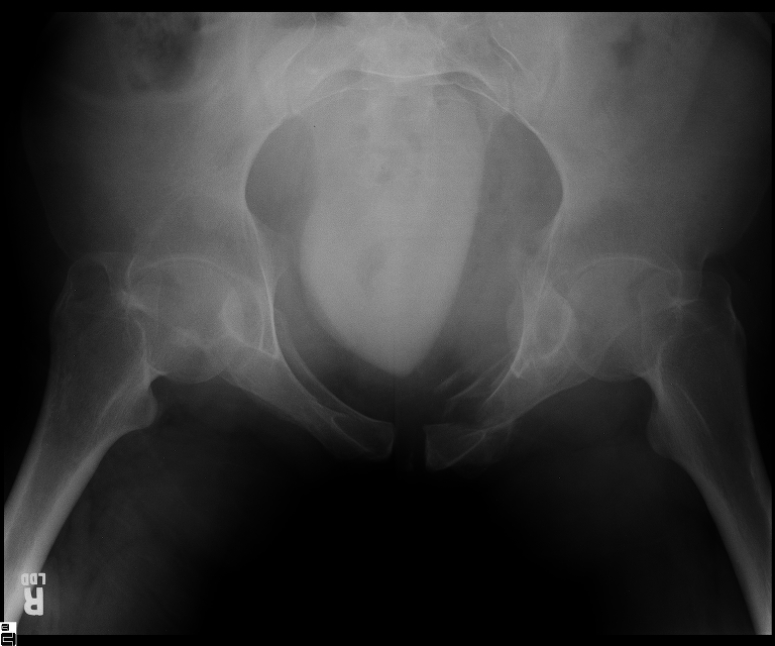

25 yo brittle diabetic, became hypoglycemic and passed out on his motorcycle. Sustained bilateral lateral Hoffa fractures with associated LCL injury on the right and right distal radius fracture. I have questions regarding his pelvic ring/acetabular fracture on the left. Appears to be a very low posterior column fracture with associated posterior wall, marginal impaction. Superior and inferior rami fractures as well on the left giving him a floating segment of inf ramus/ischium/posterior column, but no detectable posterior ring injury. Should the posterior column/posterior wall fracture be addressed surgically because of the marginal impaction? Or is this fracture low enough to be treated non-operatively? I appreciate the input.

It's an interesting case. The plain films show the impaction, but most of the joint looks pretty good. The CT cuts look awful, though.

The impaction is so big I don't think I would ignore it. It IS down low, but it takes up almost the whole southern hemisphere of his joint.